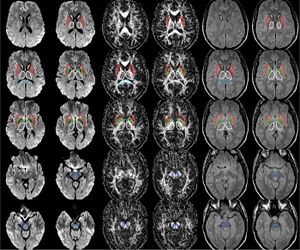

The regions-of-interest (ROIs) were manually drawn by an experienced radiologist by using the b 1000 images, averaged for all measured directions, the FA maps and the proton-density weighted images. For that purpose, the maps of ADC, FA, R2 and R2* as well as the proton-density weighted images were first co-registered. The ROIs were segmented by syncing the b 1000 images, averaged for all measured directions, the FA maps and the proton-density weighted images in ImageJ. The ROIs were stored in the ROI manager and transferred to the co-registered maps. The segmented brain regions were highlighted in different colors: CN—black; PU—red; GP—green; TH—white; SN—blue; CC—cyan. The diffusion-weighted images, the R2 and R2*-weighted maps were transferred to the 3D Slicer software in order to co-register the R2 and the R2* maps as well as the MD and the FA maps |

Publication: PLoS One. 2015 Dec 29;10(12):e0145493. PMID: 26713760 | PDF Authors: Esterhammer R, Seppi K, Reiter E, Pinter B, Mueller C, Kremser C, Zitzelsberger T, Nocker M, Scherfler C, Poewe W, Schocke M. Institution: Department of Radiology, University Hospital, Innsbruck Medical University, Innsbruck, Austria. Background/Purpose: The purpose of the present study was to evaluate the potential of multimodal MR imaging including mean diffusivity (MD), fractional anisotropy (FA), relaxation rates R2 and R2* to detect disease specific alterations in Parkinson's Disease (PD). We enrolled 82 PD patients (PD-all) with varying disease durations (≤5 years: PD≤5, n = 43; >5 years: PD>5, n = 39) and 38 matched healthy controls (HC), receiving diffusion tensor imaging as well as R2 and R2* relaxometry calculated from multi-echo T2*-weighted and dual-echo TSE imaging, respectively. ROIs were drawn to delineate caudate nucleus (CN), putamen (PU), globus pallidus (GP) and substantia nigra (SN) on the co-registered maps. The SN was divided in 3 descending levels (SL 1-3). The most significant parameters were used for a flexible discrimination analysis (FDA) in a training collective consisting of 25 randomized subjects from each group in order to predict the classification of remaining subjects. PD-all showed significant increases in MD, R2 and R2* within SN and its subregions as well as in MD and R2* within different basal ganglia regions. Compared to the HC group, the PD≤5 and the PD>5 group showed significant MD increases within the SN and its lower two subregions, while the PD≤5 group exhibited significant increases in R2 and R2* within SN and its subregions, and tended to elevation within the basal ganglia. The PD>5 group had significantly increased MD in PU and GP, whereas the PD≤5 group presented normal MD within the basal ganglia. FDA achieved right classification in 84% of study participants. Micro-structural damage affects primarily the SN of PD patients and in later disease stages the basal ganglia. Iron contents of PU, GP and SN are increased at early disease stages of PD. Funding: